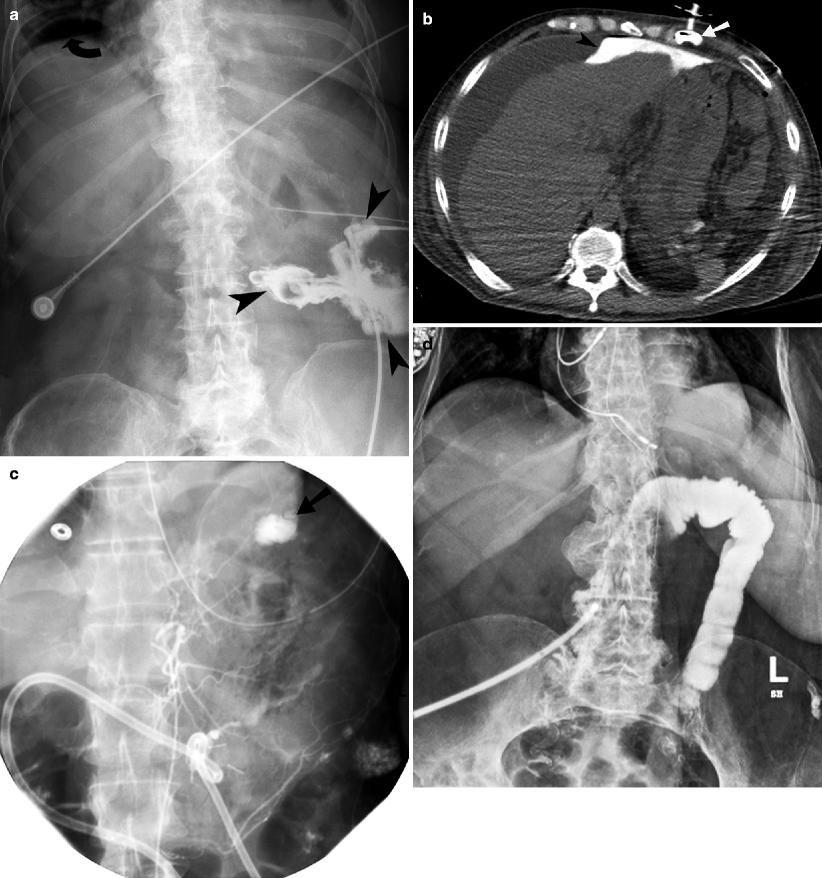

Percutaneous Radiologic Gastrostomy Using PushType Gastrostomy Tubes

Percutaneous Radiologic Gastrostomy Using PushType Gastrostomy Tubes Interventional Radiology G Tube Placement Although the safety of this procedure is well documented, complications do occur. Since the publication of the qi standards in 2014, newly reported techniques have been developed to optimize gastrostomy (g). Percutaneous endoscopic gastrostomy (peg) is a procedure where a flexible feeding tube (commonly known as a peg tube). A radiologically inserted gastrostomy (rig), or percutaneous radiological gastrostomy (rpg), is. Interventional Radiology G Tube Placement.